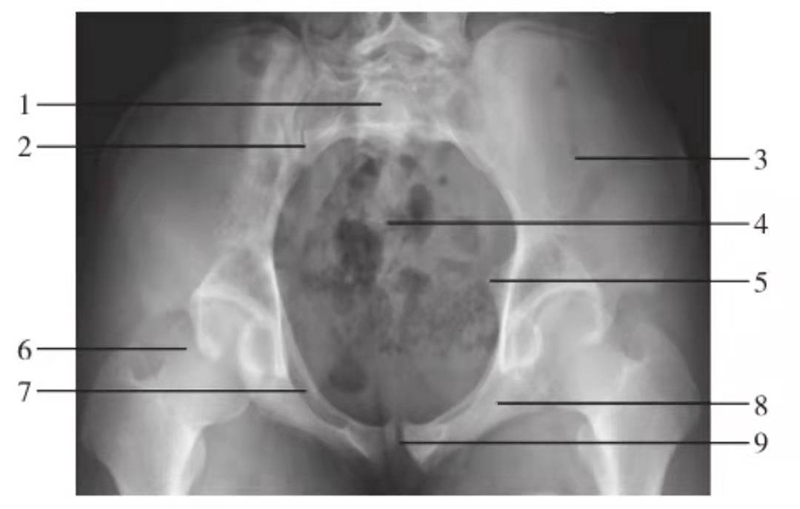

图1 髋关节正位片(生长期,9岁)

1.髂骨;2.髋关节间隙;3.Y形软骨;4.股骨头骨骺;5.骨骺板;6.临时钙化带;7.泪滴;8.大转子骨骺;9.股骨颈

图2 髋关节正位片(成人期)

1.髋臼线;2.髂坐线;3.髂耻线;4.前唇线;5.后唇线;6.泪滴